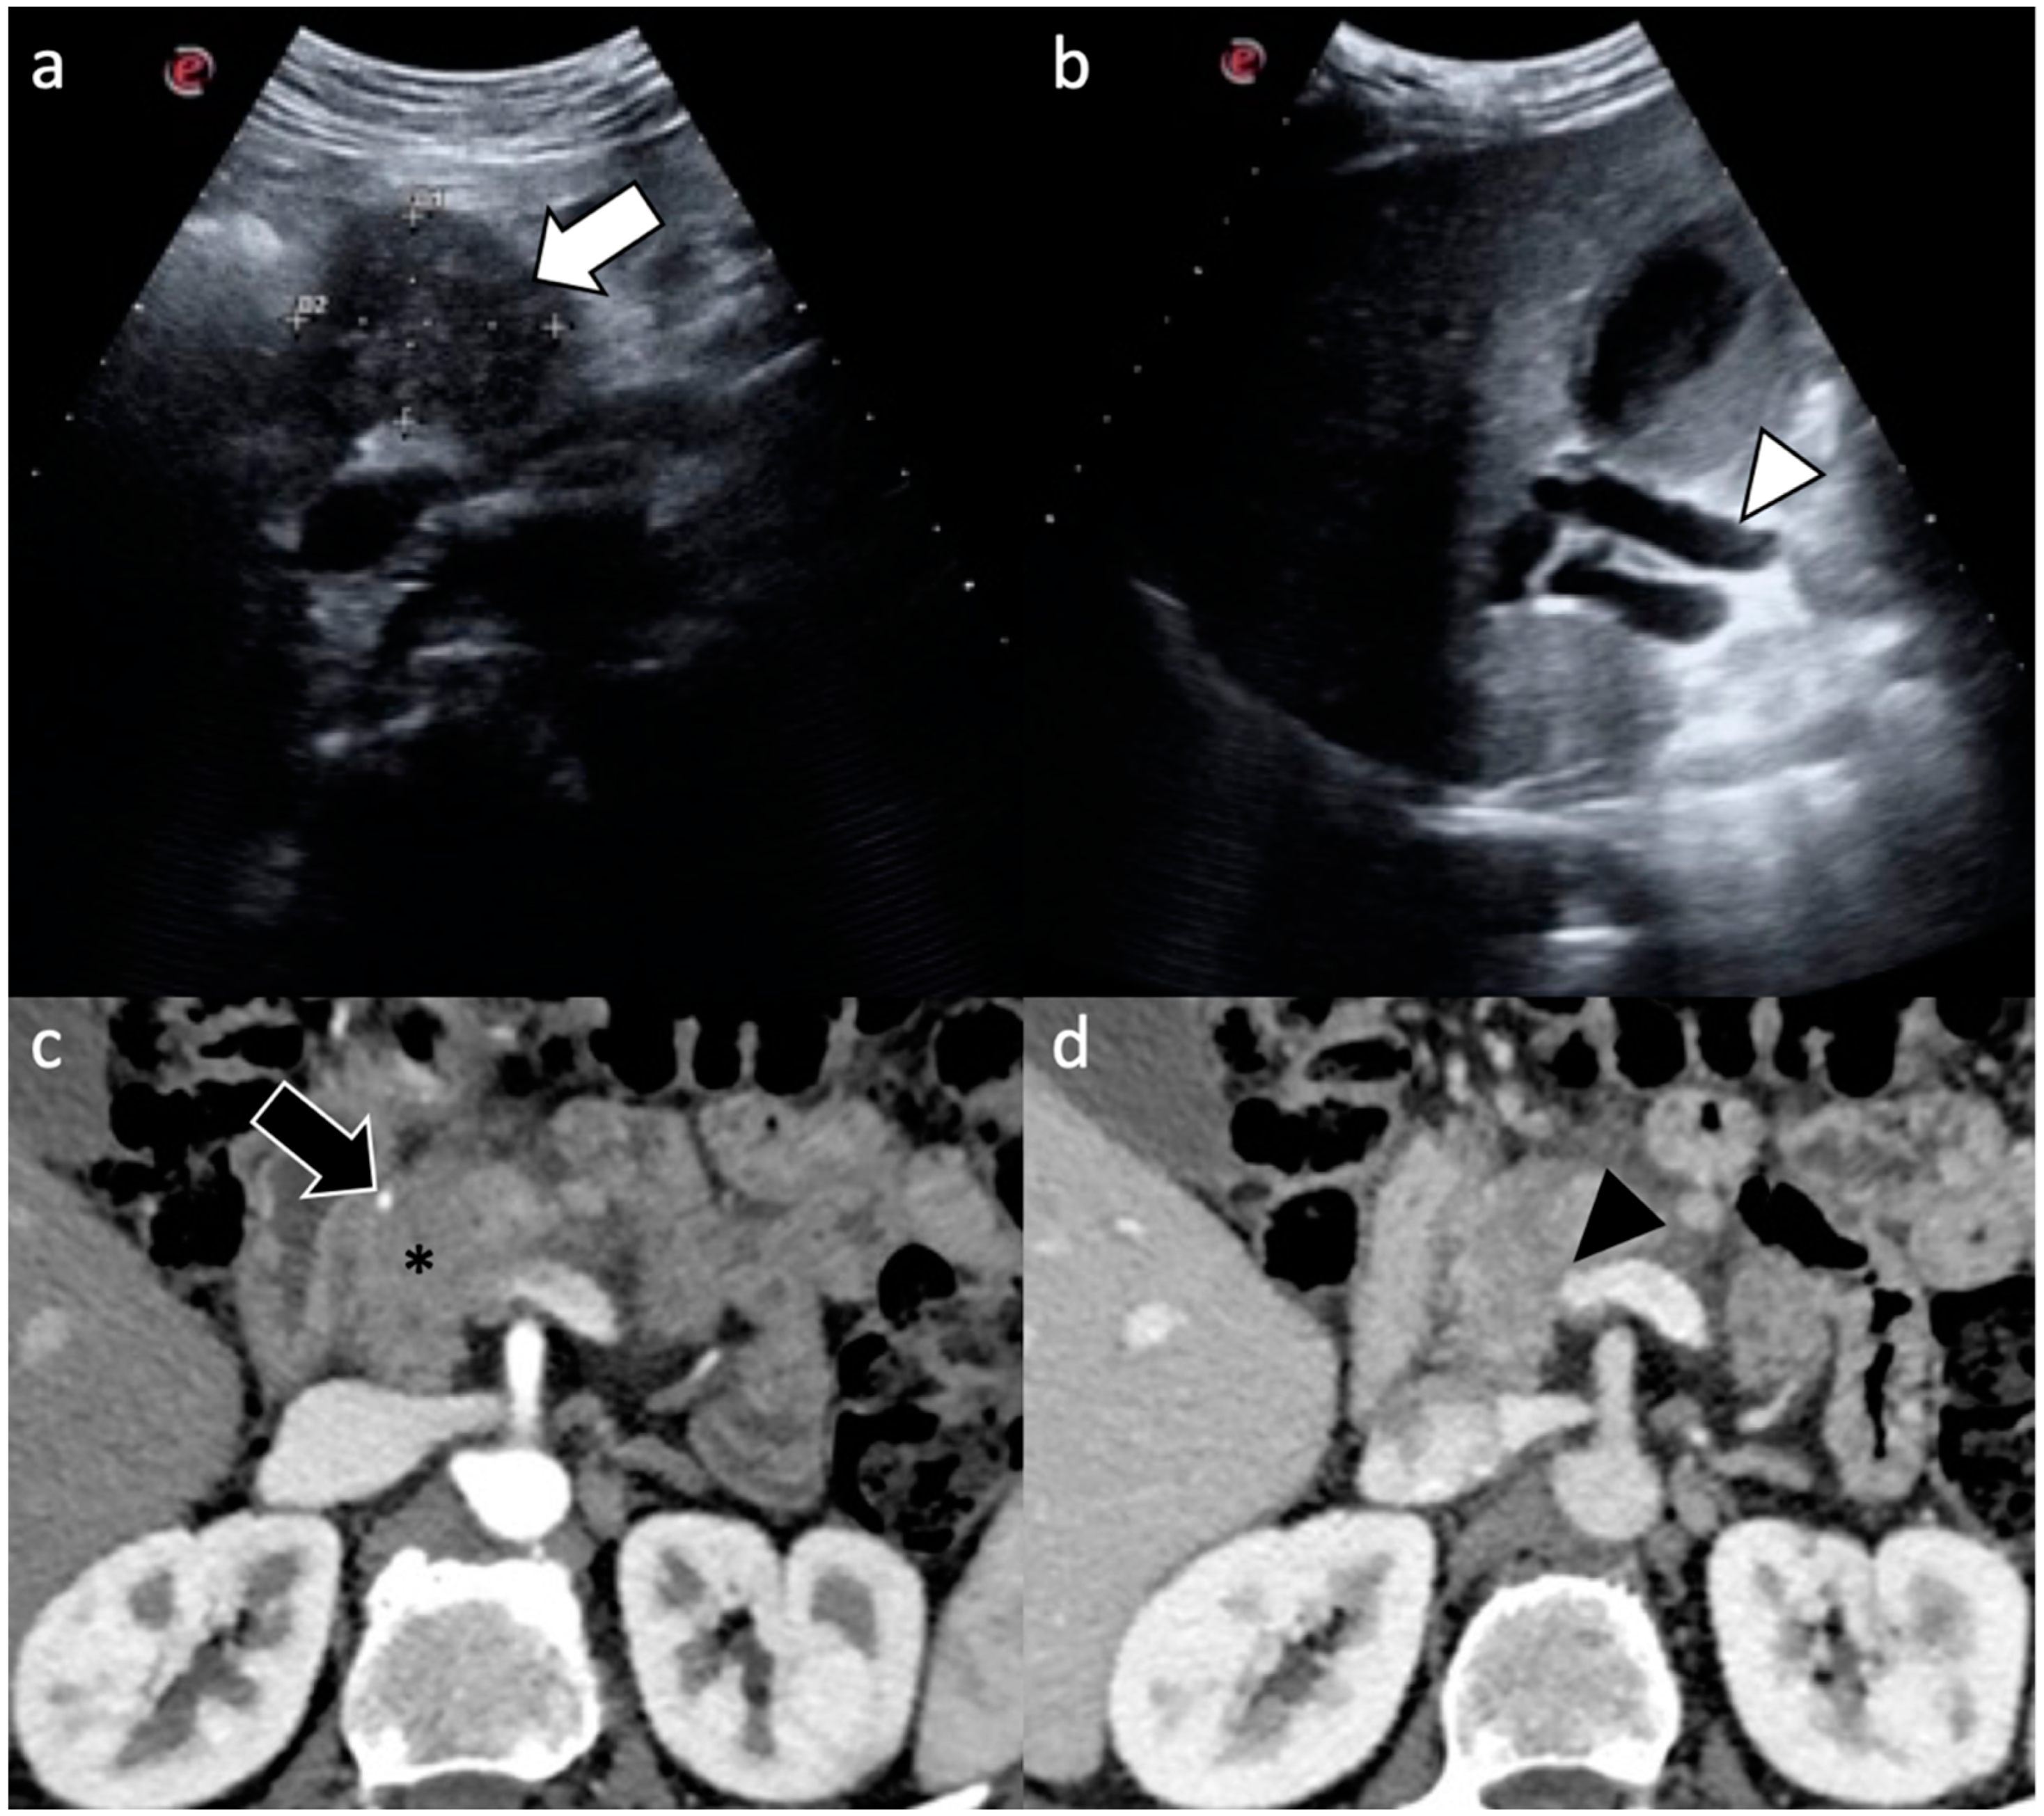

| Ultrasound |

| Computed Tomography |

| Magnetic Resonance Imaging |